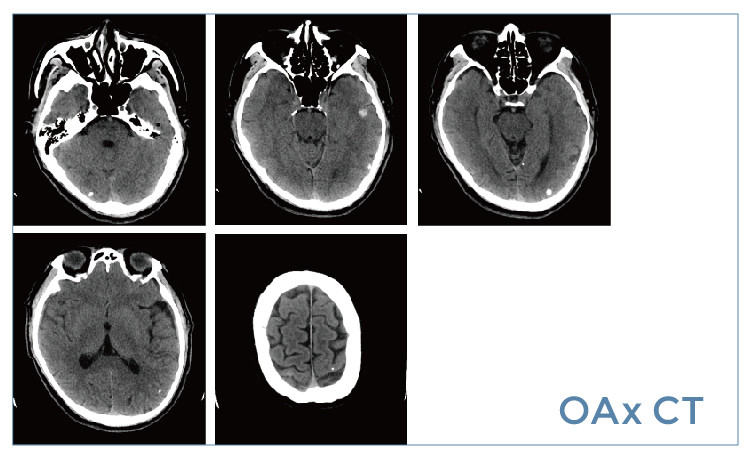

【朗润影像档案】20190621磁共振影像病例结果讨论

【朗润影像档案】磁共振影像病例分享(编号20190621)